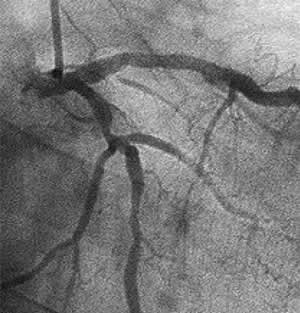

C-1 : 7 months follow-up angio

| Diagnosis: AP, SVD Present Illness: '89.10 AMI, CAG: TVD '89.11 POBA for #1 '95.7 Recurrent AP, POBA for #13 '00.8.25 POBA for #3 '01.7~ Recurrent AP |

| Final CAG Findings:01.8.1 LVG: asynergy (A), EF: 69% CAG: #6 75% |